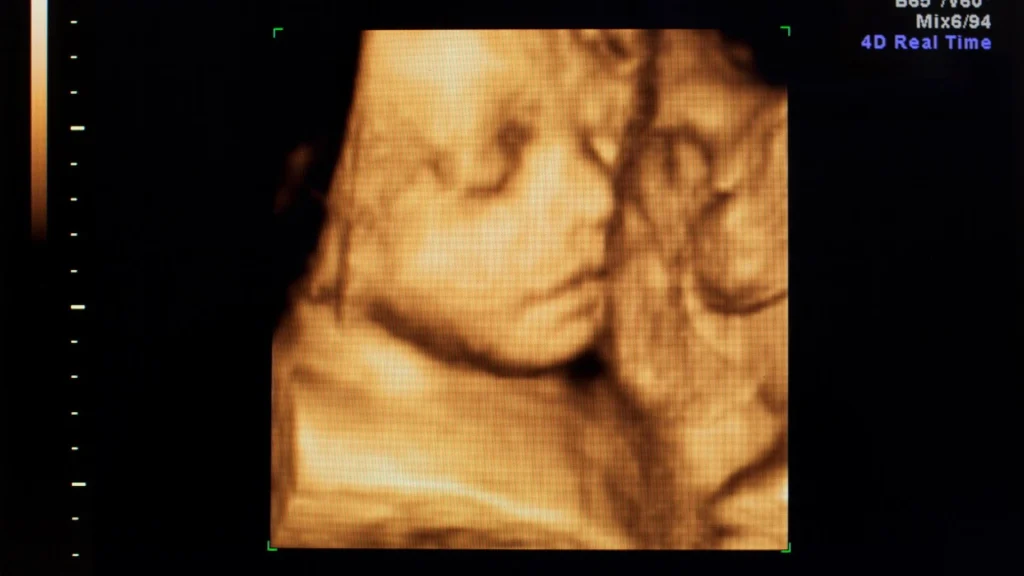

USG 5D menawarkan citra janin dengan resolusi tinggi dan gerakan real-time yang halus, memungkinkan dokter melihat anatomi secara lebih rinci. Detail ini memudahkan identifikasi struktur organ janin yang kompleks dan mendukung deteksi kelainan sejak tahap awal. Visualisasi yang jelas juga membantu orang tua memahami kondisi janin secara lebih akurat.

Pemantauan Perkembangan Janin Secara Real-Time

Teknologi 5D memungkinkan pemantauan perkembangan janin secara berkelanjutan dengan citra yang stabil dan jelas. Dokter dapat menilai fungsi organ, gerakan, dan posisi janin dari waktu ke waktu. Pendekatan ini mempermudah identifikasi perubahan dini yang mungkin memerlukan perhatian khusus.